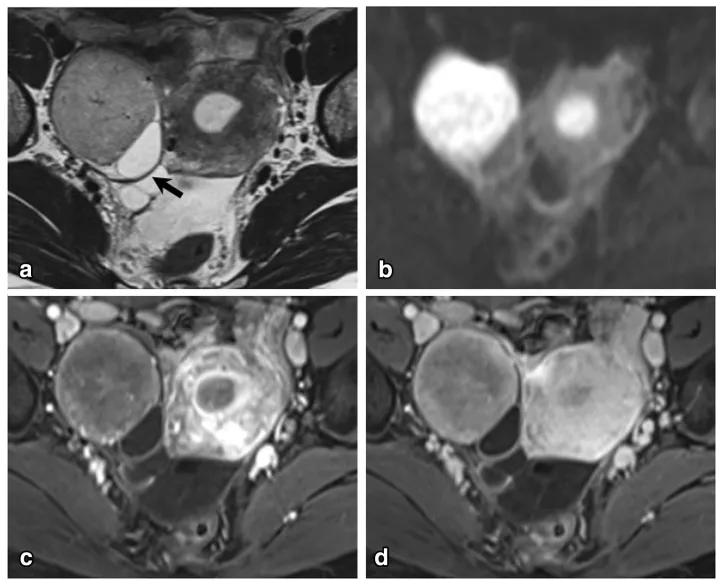

女,47 岁,卵巢子宫内膜样癌。右侧卵巢异常信号肿物,T2WI 混杂稍高及高信号(图 a),DWI 高信号(图 b),增强扫描不均匀强化(图 c)。肿物内见条片状裂隙样异常信号(箭头),T2WI 呈高信号、DWI 低信号、增强扫描未见强化。

女,64 岁,雌激素升高,卵巢子宫内膜样癌。卵巢肿物由三部分构成,偏右侧是囊性成分;中间部分(箭头)T2WI 及 DWI 呈低信号(a 及 b),增强扫描明显强化(c 增强早期,d 增强晚期);偏左侧部分 T2WI 稍高信号,DWI 高信号,增强扫描明显强化。HE 染色显示中间部分肿物由功能性纤维间质构成(图 e)。HE 染色肿瘤左侧部分显示子宫内膜样癌与性索间质肿瘤类似。矢状位显示子宫体积增大(图 g)